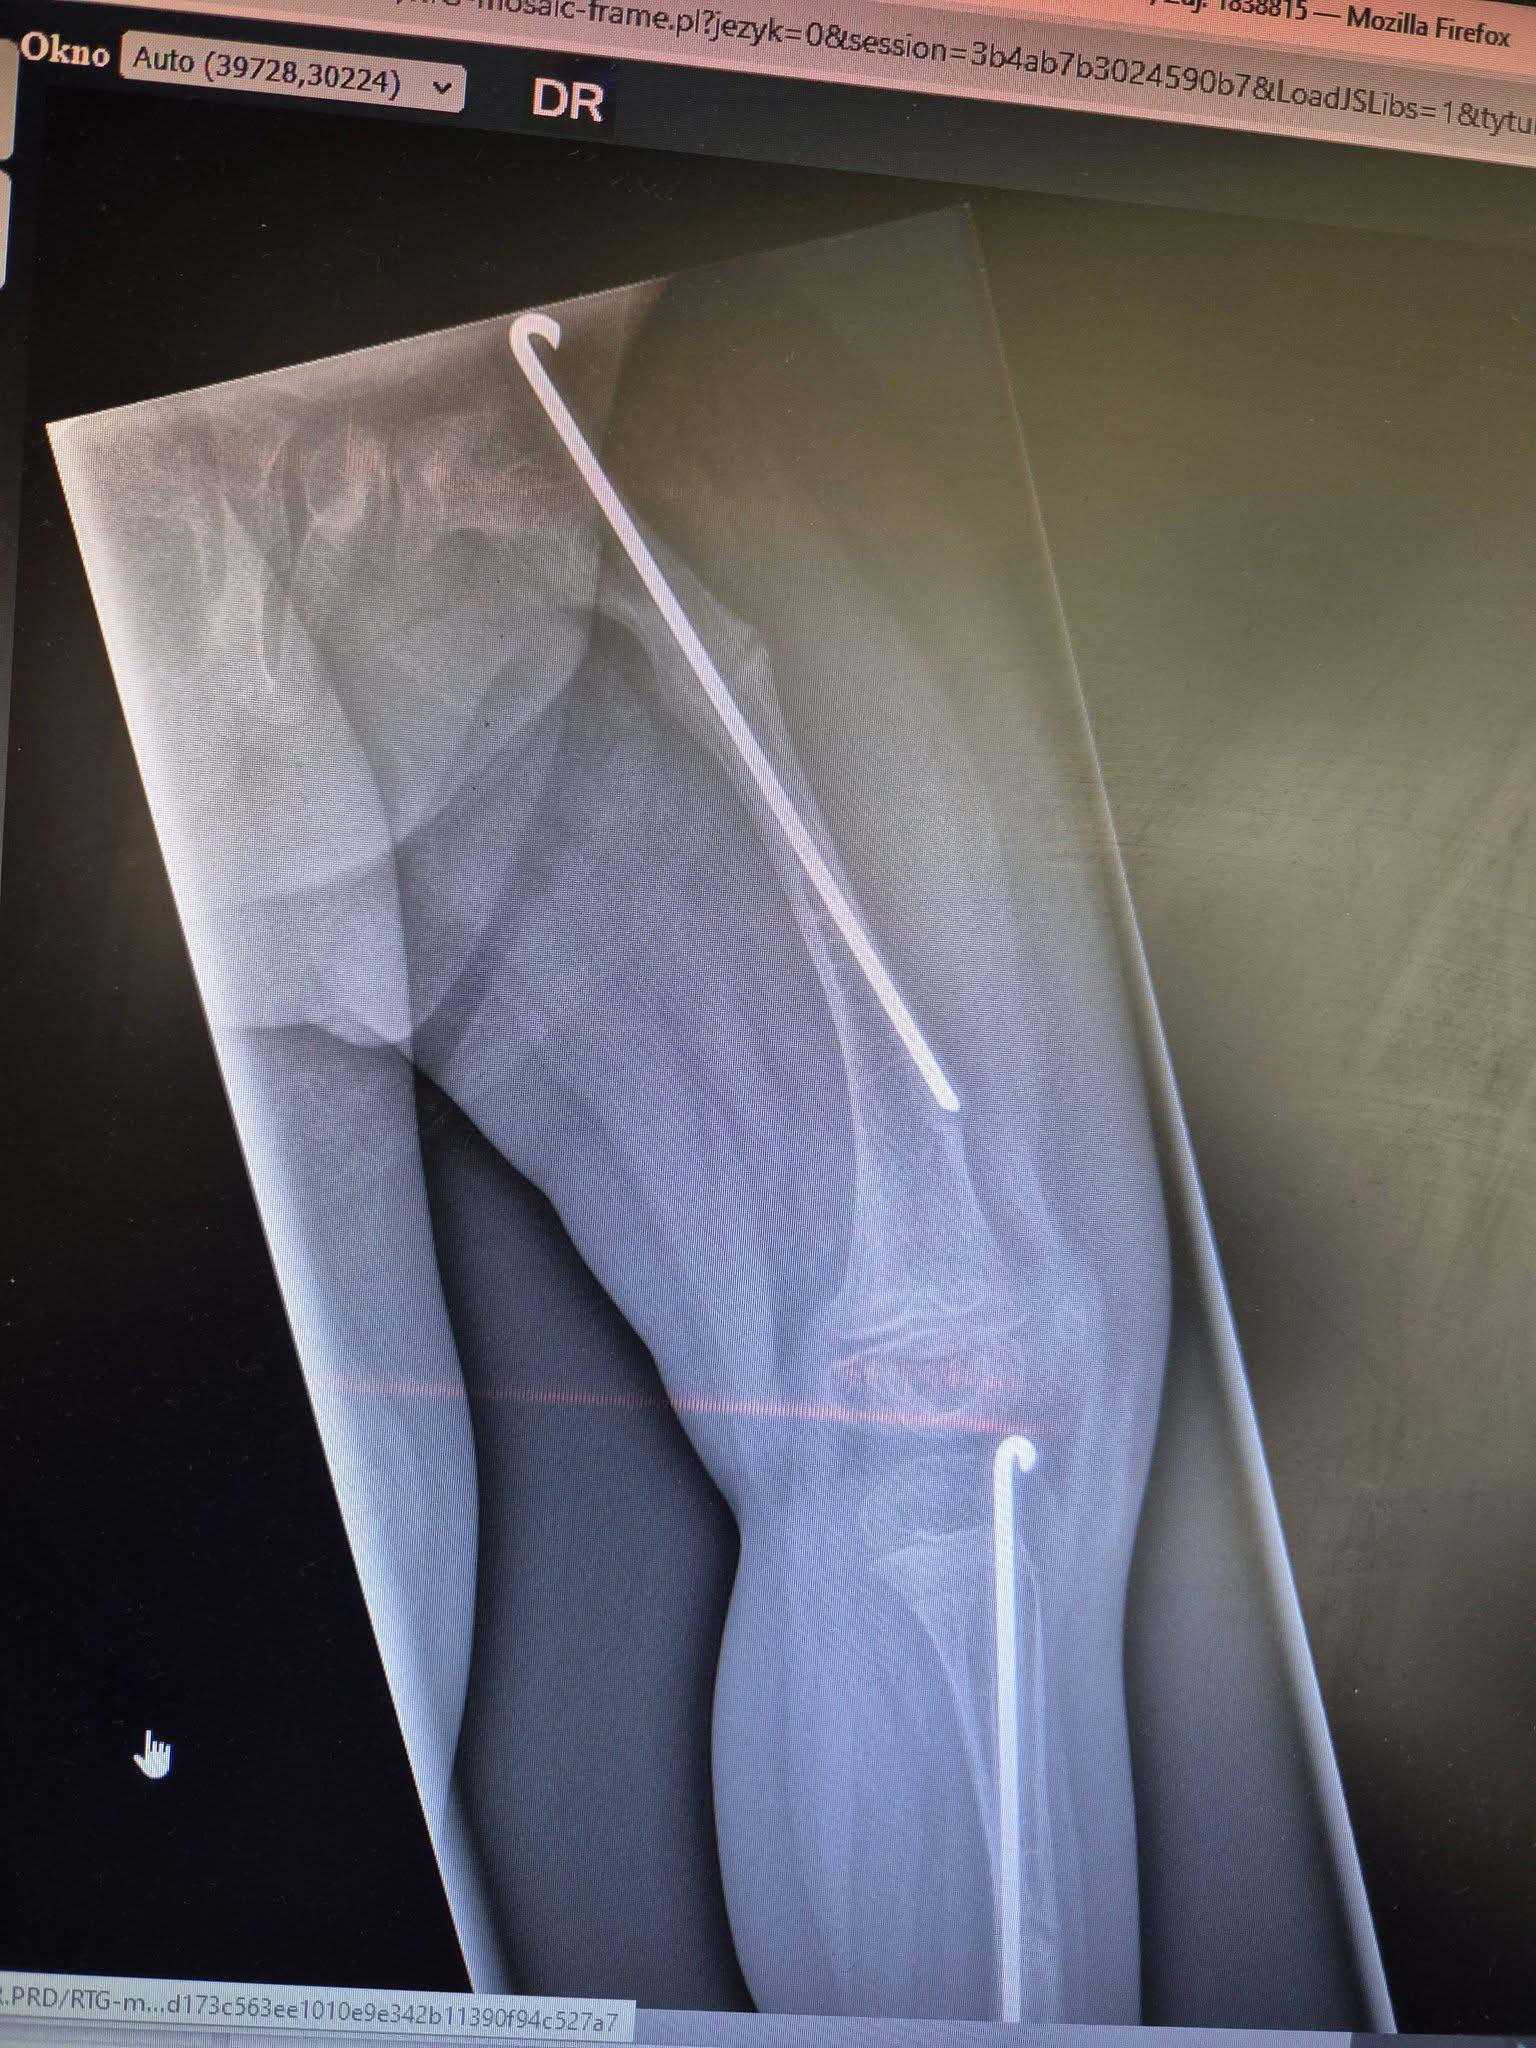

Madzia choruje na wrodzoną łamliwość kości typu III (osteogenesis imperfecta) – rzadką, genetyczną chorobę tkanki łącznej, która powoduje skrajną kruchość kości. Złamań doznała już w życiu płodowym, a jej organizm nie produkuje kolagenu. Choroba jest nieuleczalna, a leczenie ma charakter objawowy i obejmuje stałą rehabilitację, liczne operacje, stabilizację kości oraz specjalistyczną farmakoterapię. Dziewczynka ma za sobą już kilka poważnych zabiegów oraz kilkanaście podań leków wzmacniających kości. Przed nią kolejne operacje i intensywna fizjoterapia, bez której trudno byłoby myśleć o większej samodzielności.